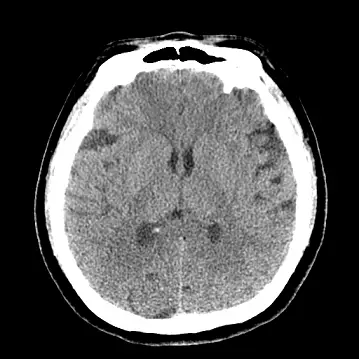

影像分析:

- 腦部 axial CT:可見散在小範圍腦挫傷與出血點,無明顯顱內大量出血或中線偏移,顯示頭部傷勢非立即致命。